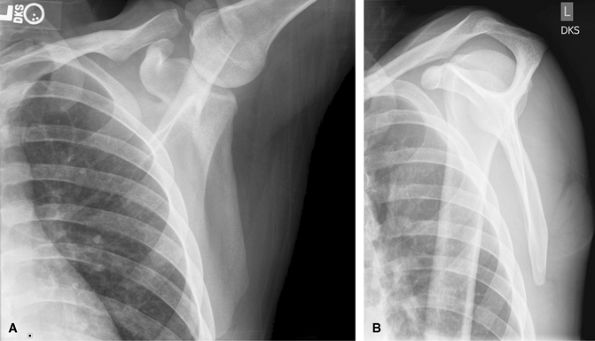

Acromioclavicular Joints

These are routinely assessed on AP shoulder views. Views

without and with weights to look for occult type 1 separations usually

do not alter management but can make the diagnosis. May be useful in

legal cases. Consider MRI to assess for deltotrapezial disruption in

type 3 or higher injuries.

![]() |

Figure 17 (A) AP without weights. (B) AP with weights.